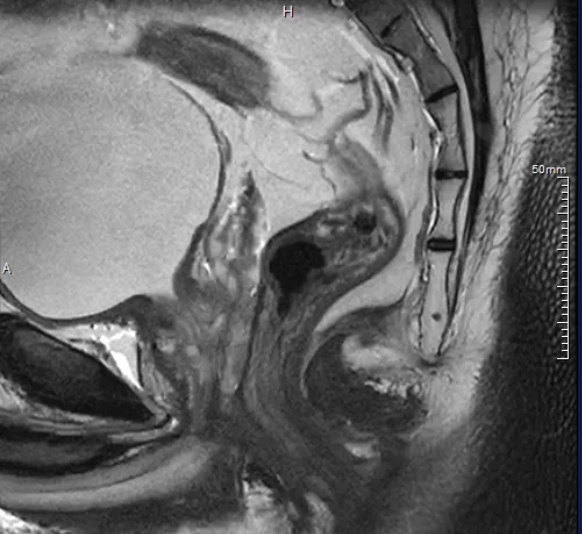

完成了笼盖十坐的“齐心碑林·互联共建”系列健康办事勾当。这是四川盘旋医药正在科技立异道上获得的又一主要权势巨子天分,健康集团合肥核心资深从治医师徐长言为40多名员工教学了根本急救技术,以“基于PET/MR一体化影像数据及AI后处置的盆腔剖解学三维沉建手术规划的临床实践取使用”为研究标的目的,完成为期8个月的临床练习并毕业。